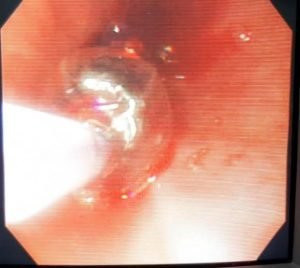

بعض النصائح الطبية عند استخدام مناظير الجهاز الهضمي لتركيب دعامة معدنية في الجزء السفلي للمرئ وفتحة الفؤاد لعلاج عدم القدرة على بلع الطعام والشراب لحالة تعاني من ورم سرطاني في الجزء السفلي للمرئ مسبباً ضيق سرطاني شديد في الجزء السفلي للمرئ وممتد إلي فتحة الفؤاد ، وفي بعض الحالات مثل هذه الحالة قد نحتاج لعمل توسيع للجزء الضيق بإستخدام بالونة التوسيع قبل تركيب الدعامة وذلك لنجاح عملية تركيب الدعامة وللحصول على أفضل النتائج، ويجب عمل هذا التوسيع بحرص ودقة لعدم حدوث نزيف أو أي مضاعفات. ويجب متابعة المرضي واستكمال علاج المرضي بعد ذلك.

Upper Gastrointestinal Endoscopy with Successful deployment of Partially Covered Antireflux Self Expandable Metallic Stent (SEMS) for treatment of Absolute Dysphagia from malignant Lower Esophageal Stricture Extending to the Cardia (Esophageal Carcinoma).

Balloon dilatation of the tight stricture was cautiously done at first, avoiding bleeding and other complications, to facilitate Successful Stent Deployment and better results. Follow up is essential for further management.